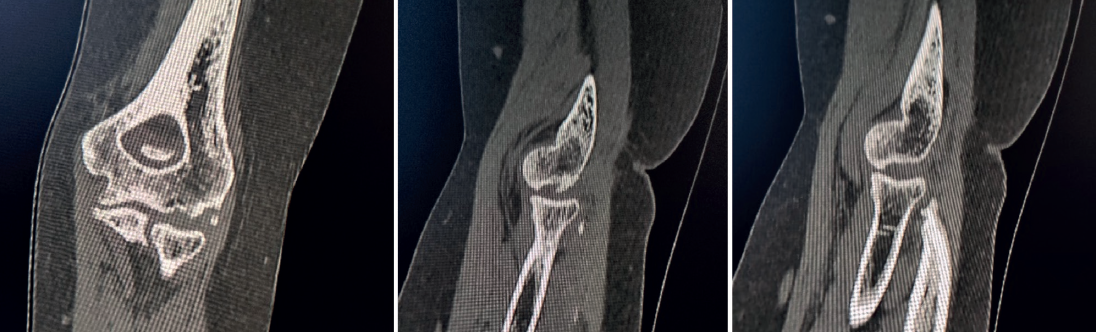

The patient was again evaluated in the clinic after 12 weeks. The physical examination revealed pain on the lateral aspect of the right elbow, with clicks on pronation, positive pivot shift manoeuvre and painful varus laxity. Complementary tests were requested: radiographs, which evidenced the Osborne-Cotterill lesion (Figure 1); a magnetic resonance imaging (MRI) scan showing distal deinsertion of the ulnar lateral collateral ligament and proximal deinsertion of the radial collateral ligament, as well as partial rupture of the annular ligament; and a computed tomography (CT) scan that found the Osborne-Cotterill osteochondral defect in the posterior capitellum to measure 8 × 3 mm (Figure 2). The patient suffered another posterior dislocation episode the following week after a new fall while undergoing rehabilitation. A second closed reduction was therefore performed.